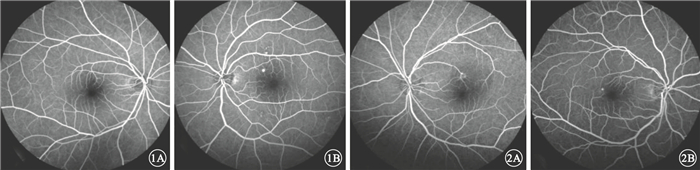

患者中,男性57例,占74.0%;女性20例,占26.0%。年齡26~63歲,平均年齡46歲。病程3 d~1年,平均病程13周。單眼發病73例,占94.8%;雙眼發病4例,占5.2%。單眼發病的73例患者中,右眼發病45例,占所有患者的58.4%;左眼發病28例,占所有患者的36.4%。急性CSC (圖 1)47只眼,占患眼的58.0%;慢性CSC(圖 2) 34只眼,42.0%。患眼視力0.12~1.0。

圖1

急性CSC患眼FFA像。1A.右眼,拱環鼻上方滲漏點,周圍呈弱熒光;1B.左眼,拱環鼻上方滲漏點,周圍呈弱熒光??圖 2?慢性CSC患眼FFA像。2A.左眼,拱環上方點狀強熒光滲漏點,周圍呈弱熒光;2B.右眼,拱環顳側點狀強熒光滲漏點,周圍呈弱熒光

圖1

急性CSC患眼FFA像。1A.右眼,拱環鼻上方滲漏點,周圍呈弱熒光;1B.左眼,拱環鼻上方滲漏點,周圍呈弱熒光??圖 2?慢性CSC患眼FFA像。2A.左眼,拱環上方點狀強熒光滲漏點,周圍呈弱熒光;2B.右眼,拱環顳側點狀強熒光滲漏點,周圍呈弱熒光

患者中,男性57例,占74.0%;女性20例,占26.0%。年齡26~63歲,平均年齡46歲。病程3 d~1年,平均病程13周。單眼發病73例,占94.8%;雙眼發病4例,占5.2%。單眼發病的73例患者中,右眼發病45例,占所有患者的58.4%;左眼發病28例,占所有患者的36.4%。急性CSC (圖 1)47只眼,占患眼的58.0%;慢性CSC(圖 2) 34只眼,42.0%。患眼視力0.12~1.0。

圖1

急性CSC患眼FFA像。1A.右眼,拱環鼻上方滲漏點,周圍呈弱熒光;1B.左眼,拱環鼻上方滲漏點,周圍呈弱熒光??圖 2?慢性CSC患眼FFA像。2A.左眼,拱環上方點狀強熒光滲漏點,周圍呈弱熒光;2B.右眼,拱環顳側點狀強熒光滲漏點,周圍呈弱熒光

圖1

急性CSC患眼FFA像。1A.右眼,拱環鼻上方滲漏點,周圍呈弱熒光;1B.左眼,拱環鼻上方滲漏點,周圍呈弱熒光??圖 2?慢性CSC患眼FFA像。2A.左眼,拱環上方點狀強熒光滲漏點,周圍呈弱熒光;2B.右眼,拱環顳側點狀強熒光滲漏點,周圍呈弱熒光